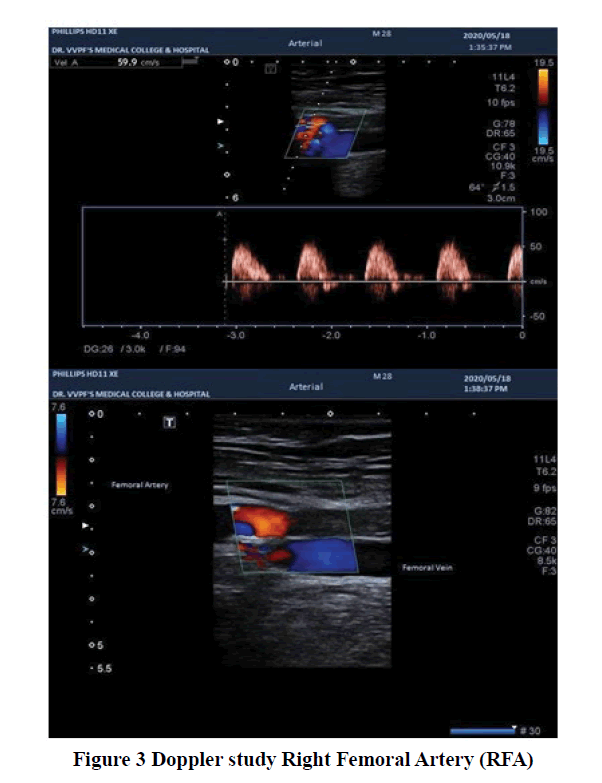

The general examination revealed a mesomorphic and averagely nourished patient. Her pulse was 90 bpm regular, normal in volume and character. Right femoral, popliteal, and dorsalis pedis pulsation were not palpable. All other peripheral pulsations were normally palpable. Her Blood Pressure (BP) was 120/70 mm Hg in the right arm supine position, respiratory rate 21 per min, and oxygen saturation (SpO2) was 98% on room air. There was no pallor, icterus, clubbing, central cyanosis, and lymphadenopathy. JVP was normal. The right lower limb was cold and clammy and there was edema up to mid-thigh. There was no definite line of demarcation at the time of admission (Figure 1). There was diffuse tenderness which aggravated active and passive limb movements. Systemic examination including that of CVS was unremarkable. Routine investigations revealed hemoglobin 10 gm/dl, Total Leucocyte Count (TLC) 5200/ mm3 (polymorphs 75%), and platelets 2.72 × 105/mm3. Total bilirubin was 0.5 mg/dl, AST-107 IU/L and ALT-91 IU/L. Serum urea was 21 mg/dl and creatinine 0.7 mg/dl. Prothrombin Time (PT) was 14.9 sec and International Normalised Ratio (INR) 1.3. The ultrasound scan of the abdomen was normal. She had no history of any drug intake, apart from ART, that could cause a procoagulant state. HBsAg, HCV RNA, VDRL and TORCH tests were negative. Autoimmune profile, comprising of ANA, APLA, Anti-Cardiolipin antibodies, and rheumatoid factors was negative. Tuberculosis was ruled out with negative sputum AFB/CBNAAT and negative Mantoux test (an induration of 03 mm at 72 hours). Chest X-ray PA view was normal (Figure 2). Echocardiography and Doppler studies of the heart were unremarkable. AV Doppler of the right lower limb demonstrated near-total thrombosis of common femoral artery, popliteal artery, and anterior & posterior tibial arteries. The right external iliac artery was patent and blood vessels of the other limbs were normal (Figure 3, and Figure 4). Ankle-Brachial Index of the affected limb couldn’t be calculated due to the absence of pulse and that of the left lower limb was 1.1.